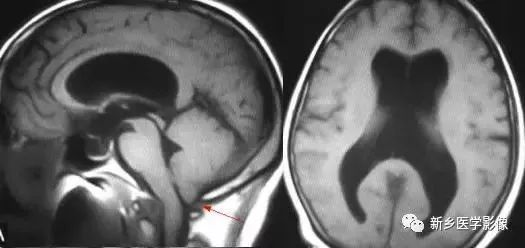

前脑无裂畸形(holoprosencephaly):是指一系列位于中线程度不同的畸形,累及大脑、面部、脑于和小脑。前脑未能够分开,呈不全性或完全性,端脑和间脑无法区分。根据脑及面部畸形程度将其分为无叶型、半叶型和单叶型。

· 无叶型前脑无裂畸形:最严重,端脑半球间没有裂隙,呈马蹄形或新月形扩大的单脑室跨越中线,与背侧囊交通。丘脑互相融合,面部畸形可有两眼距离过近、独眼畸形等。往往死于胎儿或新生儿期。

· 半叶型前脑无裂畸形:在前脑可见部分裂隙, 形成不同发育程度的大脑纵裂及大脑镰。两侧大脑半球在前部未完全分开,但枕叶和 双侧侧脑室体部分离,丘脑分开不完全。三脑室和海马发育不全,胼胝体仅可见到压部,而其他部分缺如额叶和基底节前部分辨不清。临床表现有两眼距离过近、唇裂、腭裂等面部畸形,侧脑室呈单一性且明显扩大。

· 单叶型前脑无裂畸形:与正常发育脑仅有些很小的区别,如透明隔缺如或双侧额叶不完全分开。